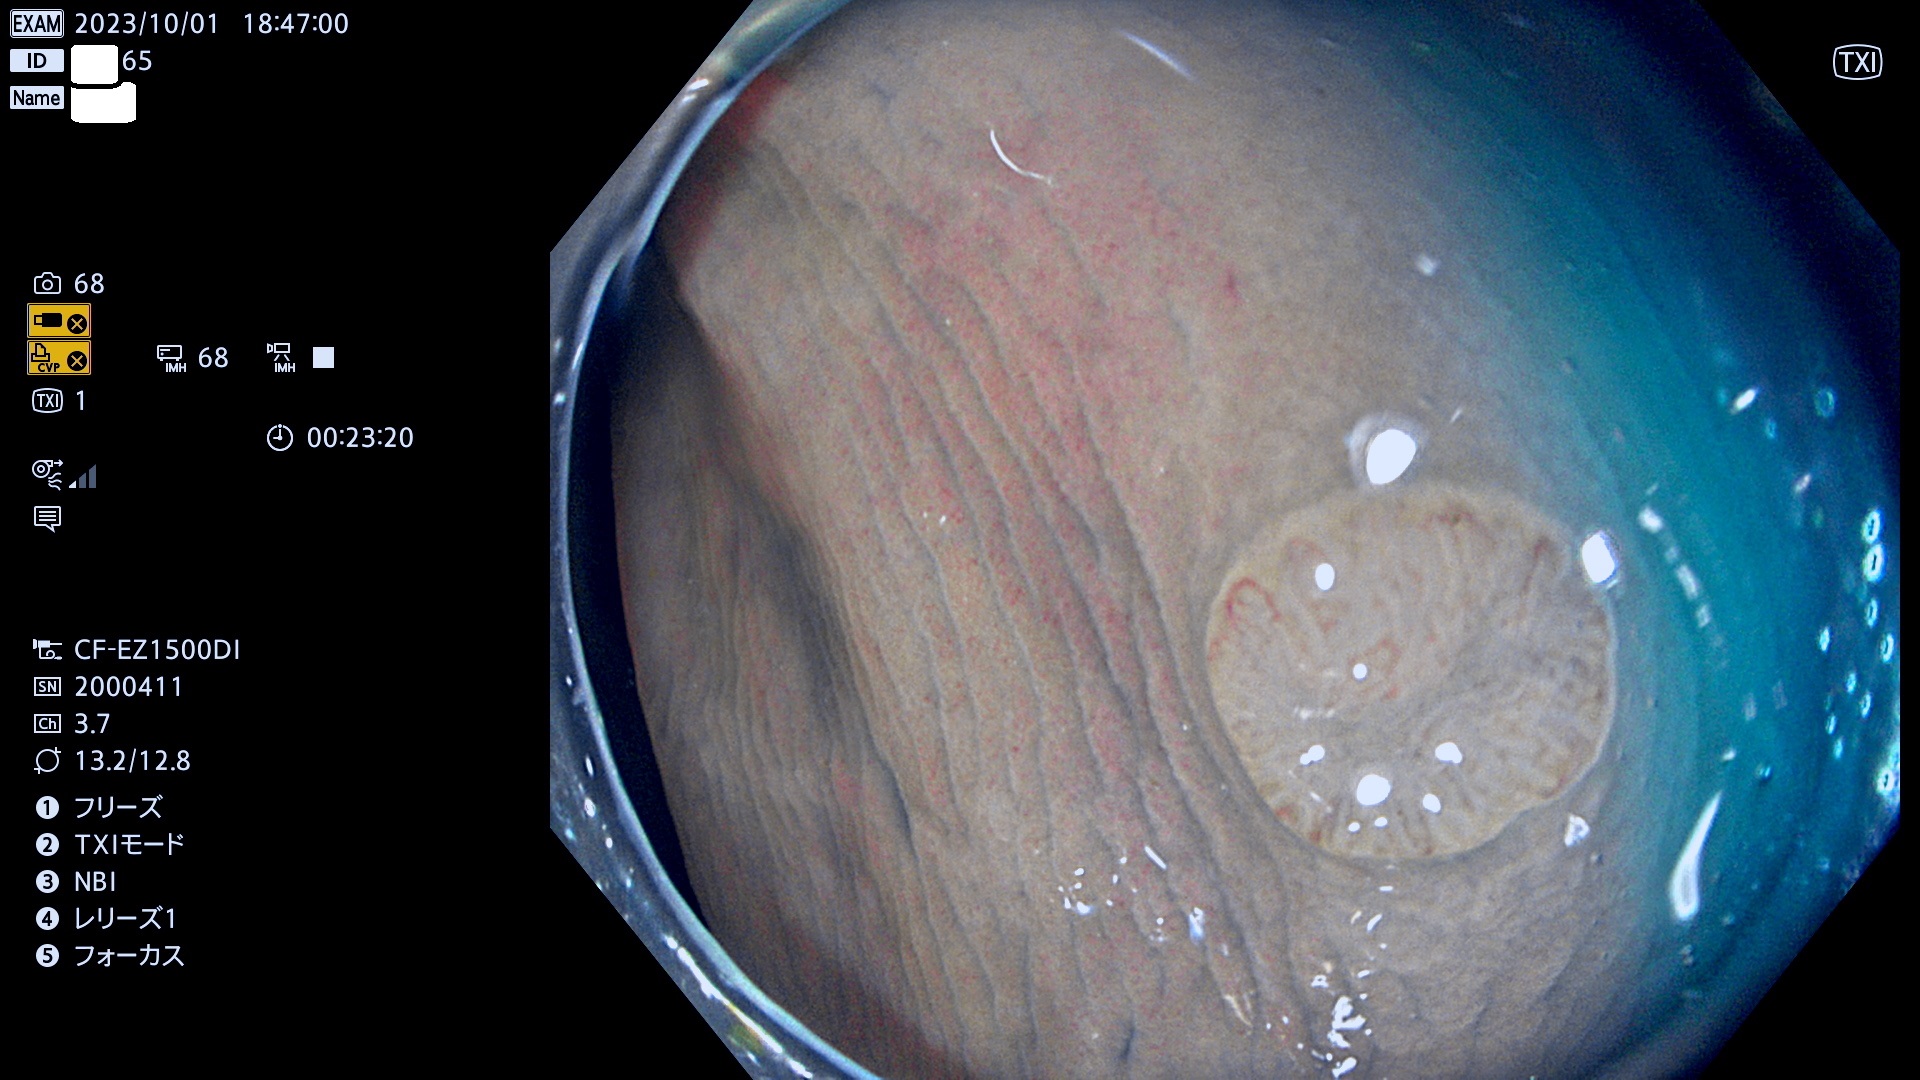

表面型腺腫(Flat Adenoma)の中で、完全に平坦な物をUb、陥凹している物をUcと呼びます。平坦隆起型(Ua)よりも、発見が難しく危険な病変です。このタイプは「内視鏡後・大腸癌の重要犯人」であり、この発見率は「腺腫発見率」よりも、重要な意味があります。

毎週の検査(木・金・土・日)に発見されたUb、Uc型・腺腫を、その週の日曜の夜にUPし1週間、提示します。

抽出の対象期間 2023年9月28日(木)〜10月1(日)の4日間(48件の検査)8件